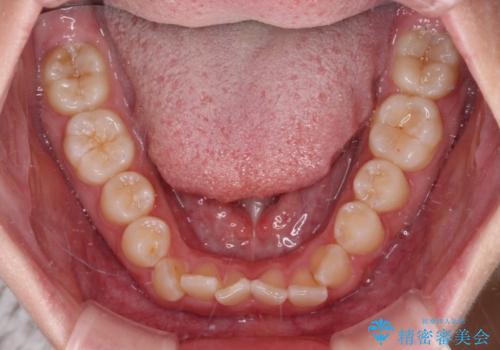

- 上下前歯のデコボコを気にして来院された患者様です。

叢生は軽度であり、ワイヤー矯正でもマウスピース矯正でも対応可能であったので、好きな装置を選んでもらいました。

相談の結果、インビザラインによる矯正治療を行うこととしました。